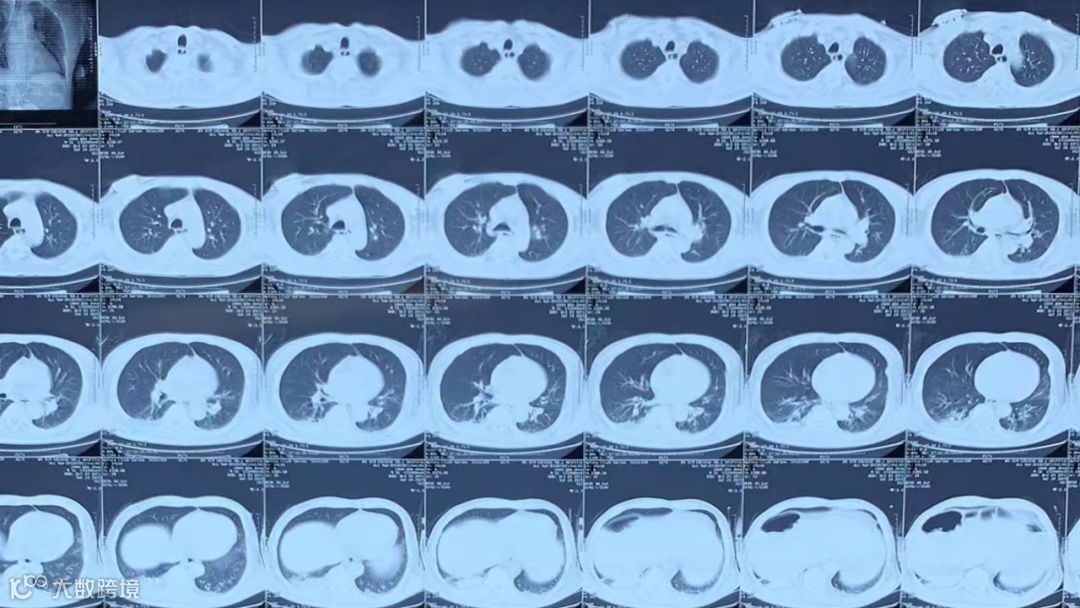

现病史:入院2天前,患者于“XX医院”住院时无明显诱因出现发热,测量体温最高42.0℃,伴寒战,恶心、呕吐,呕吐物为胃内容物。予退热药,仍反复发热,呼吸急促,间断四肢强直,行“肺泡灌洗液”NGS检查检出“金黄色葡萄球菌、鲍曼不动杆菌、白念珠菌”(图1),CT提示双下肺坠积性肺炎(图2),血常规提示血象高、血小板低,给予“万古霉素、比阿培南”抗感染治疗。1天前出现心率快、血压低,尿量减少,血小板极低,为进一步诊治,转入我院就诊。以“脓毒血症”经急诊收入我科。

图2. 入院前外院肺CT检查